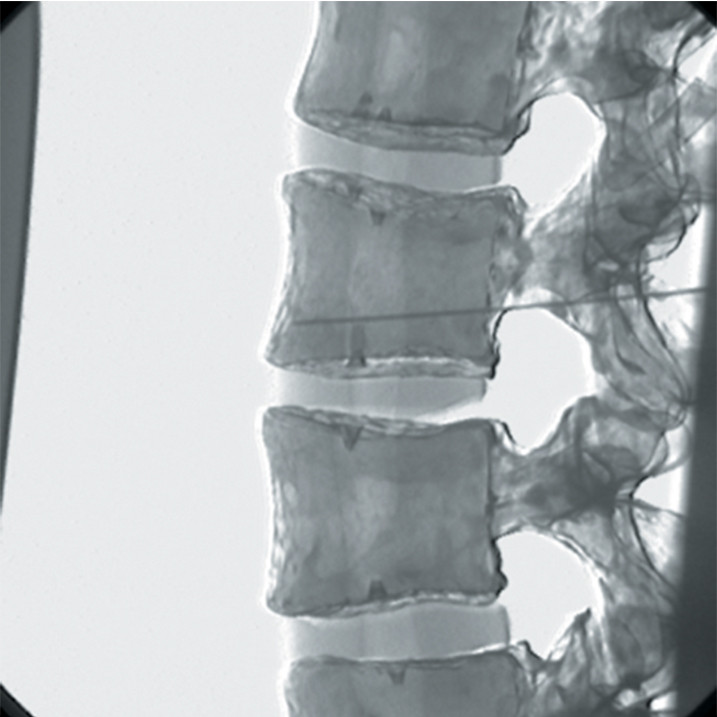

Spinal Pain Relief in Smithtown Block Sports Chiropractic & PT Block Pain Relief Often a group of nerves, called a plexus or ganglion, that causes. While generally safe, epidurals can have side effects like headache or infection. It relieves pain by interrupting how pain signals are sent to your brain. Epidural nerve blocks are highly effective for targeted pain relief. Nerve blocks ease pain by offering immediate relief. Discuss these with your healthcare. Block Pain Relief.